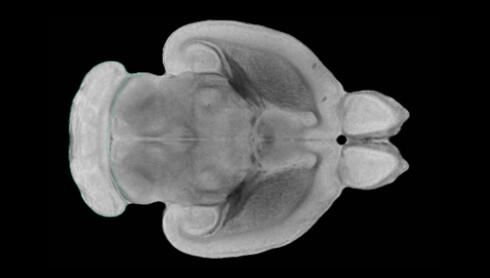

隨著機(jī)體年齡增加,肌肉和關(guān)節(jié)都會(huì)變得僵硬,這就會(huì)使得日常活動(dòng)變得更加困難,本文研究表明,我們的大腦也是如此,與年齡相關(guān)的大腦僵硬對(duì)大腦干細(xì)胞的功能或許有著重要影響。文章中,研究人員對(duì)年輕和老化大鼠的大腦進(jìn)行研究闡明了年齡相關(guān)大腦僵硬對(duì)少突膠質(zhì)前體細(xì)胞(OPCs,oligodendrocyte progenitor cells)功能的影響。OPCs是一類對(duì)維持正常大腦功能非常重要的大腦干細(xì)胞,其對(duì)于髓磷脂的再生也非常重要,髓磷脂是神經(jīng)組織周圍的脂肪鞘,在多發(fā)性硬化癥中髓磷脂的再生常常會(huì)被損傷,機(jī)體老化對(duì)這些細(xì)胞的影響常常會(huì)誘發(fā)多發(fā)性硬化癥的發(fā)生,這些細(xì)胞的功能在老化的健康人群中同樣會(huì)下降。

為了確定老化OPCs的功能缺失是否可以被逆轉(zhuǎn),研究人員將來(lái)自老化大鼠機(jī)體的老化OPCs轉(zhuǎn)移到了年輕大鼠柔軟的海綿狀大腦組織中去,值得注意的是,這些老化的大腦細(xì)胞能夠重新恢復(fù)活力,其行為非常像年輕更加強(qiáng)壯的細(xì)胞。這項(xiàng)研究中,研究人員在實(shí)驗(yàn)室中開發(fā)出了具有可變僵硬程度的新型材料,并在受控環(huán)境下研究這些材料的生長(zhǎng)及其對(duì)大鼠大腦干細(xì)胞的影響,這些材料能被工程化改造具有和年齡或老化大腦相似的柔軟程度。